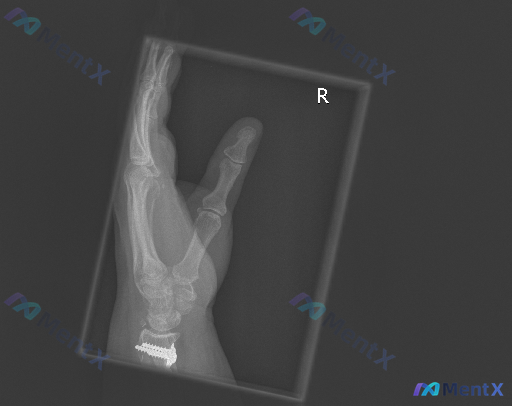

这张右手斜位X线片,除了内固定之外还要警惕什么?

整理到一份右手斜位X线片的影像分析资料,觉得很适合拿出来讨论阅片思维。

- 投照是右手斜位,拇指和四指分开,但手指有重叠

- 最显眼的是腕关节区域有金属内固定(钢板+多枚螺钉),位置看起来还行,没看到明显断裂松动

- 第1-5掌骨、拇指近远节指骨,在可见范围内没看到明确的皮质中断或错位

- 掌指关节、指间关节对合也还好

- 骨密度、软组织(除了内固定)也没特别异常

报告给出的总结是「右侧腕关节内固定术后改变;手部掌骨及可见指骨未见明确新鲜骨折征象;关节对合良好」,建议结合既往片对比、必要时加拍正侧位或CT。

但这份资料里的核心看点其实不在「没看到什么」,而在「不能轻易排除什么」——

- 斜位片的重叠会不会盖掉细微骨折?

- 没有既往片,能100%确定内固定没松动吗?

- 如果患者还有局部疼痛,平片「阴性」就够了吗?

📋答案:优先「历史影像对比」+「多体位联合摄片」,无对比不结论;结合临床症状必要时行CT/MRI及实验室检查。